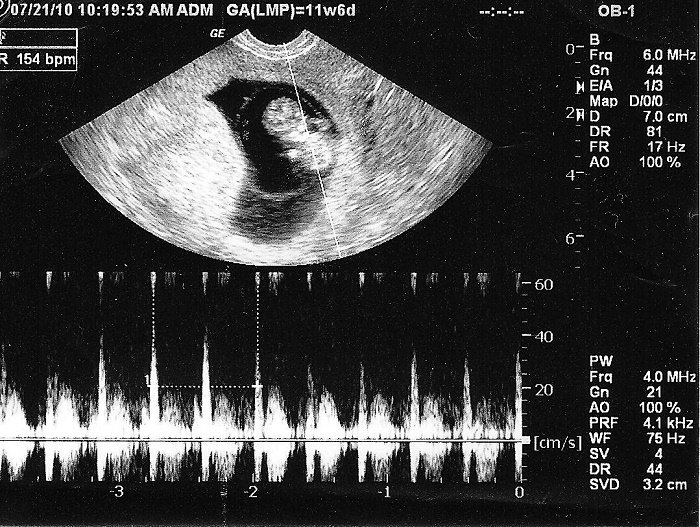

Đến tuần thứ 7, tim thai nhi lớn bắt đầu phân chia thành buồng trái và buồng phải. Nhịp đập khoảng 90–110 nhịp/phút và tăng lên mỗi ngày. Vào khoảng tuần thứ 9, nhịp tim thai đạt đỉnh điểm, từ 140–170 nhịp/ phút ở cả bé trai lẫn bé gái.

Vào tuần 11-12 của thai kỳ, tim thai nhi gần như hoàn thiện. Bước sang tuần 16, tim thai có thể bơm 24 lít máu/ngày. Lượng máu tim co bóp cũng sẽ tăng lên cùng sự phát triển của thai nhi đồng thời tim cũng hoàn chỉnh về mặt cấu tạo, chức năng, tăng khối lượng, kích thước.

Nhịp tim thai bình thường đập từ 120 – 160 nhịp /phút.

Vào tuần 16, nhịp tim thai trung bình là 120 - 160 lần/phút và có thể tăng lên 180 lần/ phút khi em bé cử động nhiều. Theo các chuyên gia sản khoa thì giai đoạn chuyển dạ, nhịp tim thai nhi tốt nhất khi đạt từ 110 - 160 nhịp/phút.

Theo các nghiên cứu, trong 3 tháng đầu bé trai có nhịp tim trung bình khoảng 154,9 bpm - sai số tới 22,8 bpm, trong khi em bé gái có nhịp tim trung bình là 151,7 bpm và sai số là 22,7 bpm. Như vậy có nghĩa, dự đoán giới tính thai nhi không thể dựa vào nhịp tim mà phải sử dụng các phương pháp như: